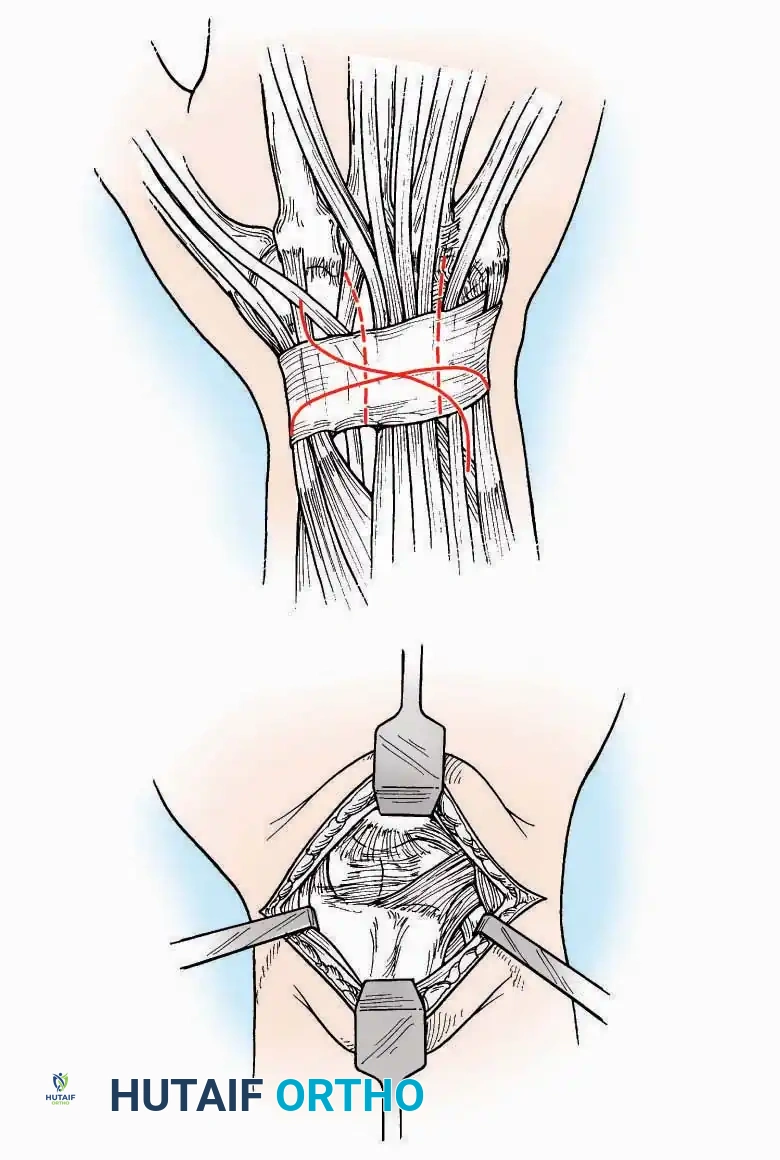

SURGICAL APPROACHES TO THE TARSUS AND ANKLE

Anterolateral Approach

The anterolateral approach is widely considered the "universal incision" for the foot and ankle. It provides unparalleled access to the ankle joint, the talus, and the majority of the tarsal articulations, while safely avoiding the major anterior neurovascular bundle. The only tarsal joints inaccessible via this route are the naviculocuneiform joints (specifically the medial and intermediate).

Indications: Total talectomy, triple arthrodesis, ankle arthrodesis, and open reduction of complex talar neck fractures.

Surgical Technique:

* Incision: Begin over the anterolateral aspect of the leg, medial to the fibula and 5 cm proximal to the ankle joint line. Carry it distally over the joint, crossing the anterolateral aspect of the talar body and the calcaneocuboid joint, terminating at the base of the fourth metatarsal.

* Superficial Dissection: Incise the superficial fascia and the superior and inferior extensor retinacula down to the periosteum of the tibia and the ankle joint capsule.

* Vascular Ligation: This trajectory usually requires the identification and ligation of the anterolateral malleolar and lateral tarsal arteries.

* Nerve Protection: Retract the skin edges carefully. Identify and protect the intermediate dorsal cutaneous branches of the superficial peroneal nerve (SPN), which frequently cross the distal aspect of this incision.

* Muscle Management: Identify the origin of the extensor digitorum brevis (EDB) muscle on the lateral calcaneus. Divide it in the direction of its fibers, or detach its origin entirely and reflect it distally to expose the subtalar and calcaneocuboid joints.

* Deep Exposure: Retract the extensor digitorum longus (EDL) tendons, the dorsalis pedis artery, and the deep peroneal nerve (DPN) medially. Incise the anterior ankle capsule to expose the tibiotalar joint.

* Tarsal Exposure: Expose the talonavicular joint by dissecting deep to the extensor tendons and incising its capsule transversely. Continue laterally through the capsule of the calcaneocuboid joint. By excising the fat pad within the sinus tarsi (lateral and inferior to the talar neck), the posterior facet of the subtalar joint is brought into direct view.